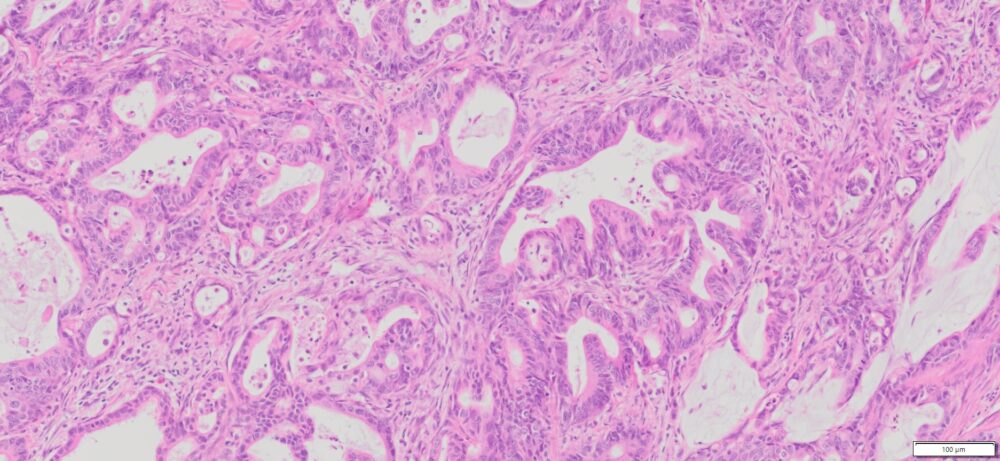

Description

| Tissue | Pathology Diagnosis | Gender/Age (year) | % Tumor area | Tumor Grade | TMN Stage | IHC Data |

| Human Colon | Colon moderately differentiated adenocarcinoma | Female/67 | 35% | II | pT4apN2pM1c | NA |

Images for H&E Stain and IHC